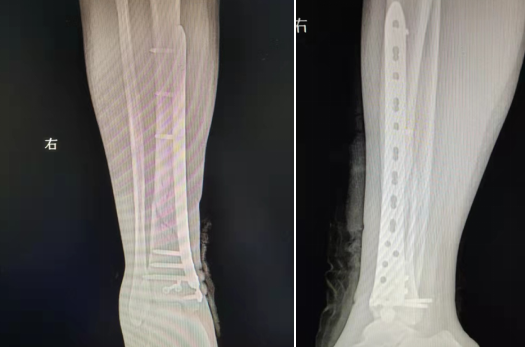

典型病例:女性,56歲,術前CT提示脛骨中下段骨折,移位明顯。

術后正側位片提示骨折達解剖復位,力線恢復正常。